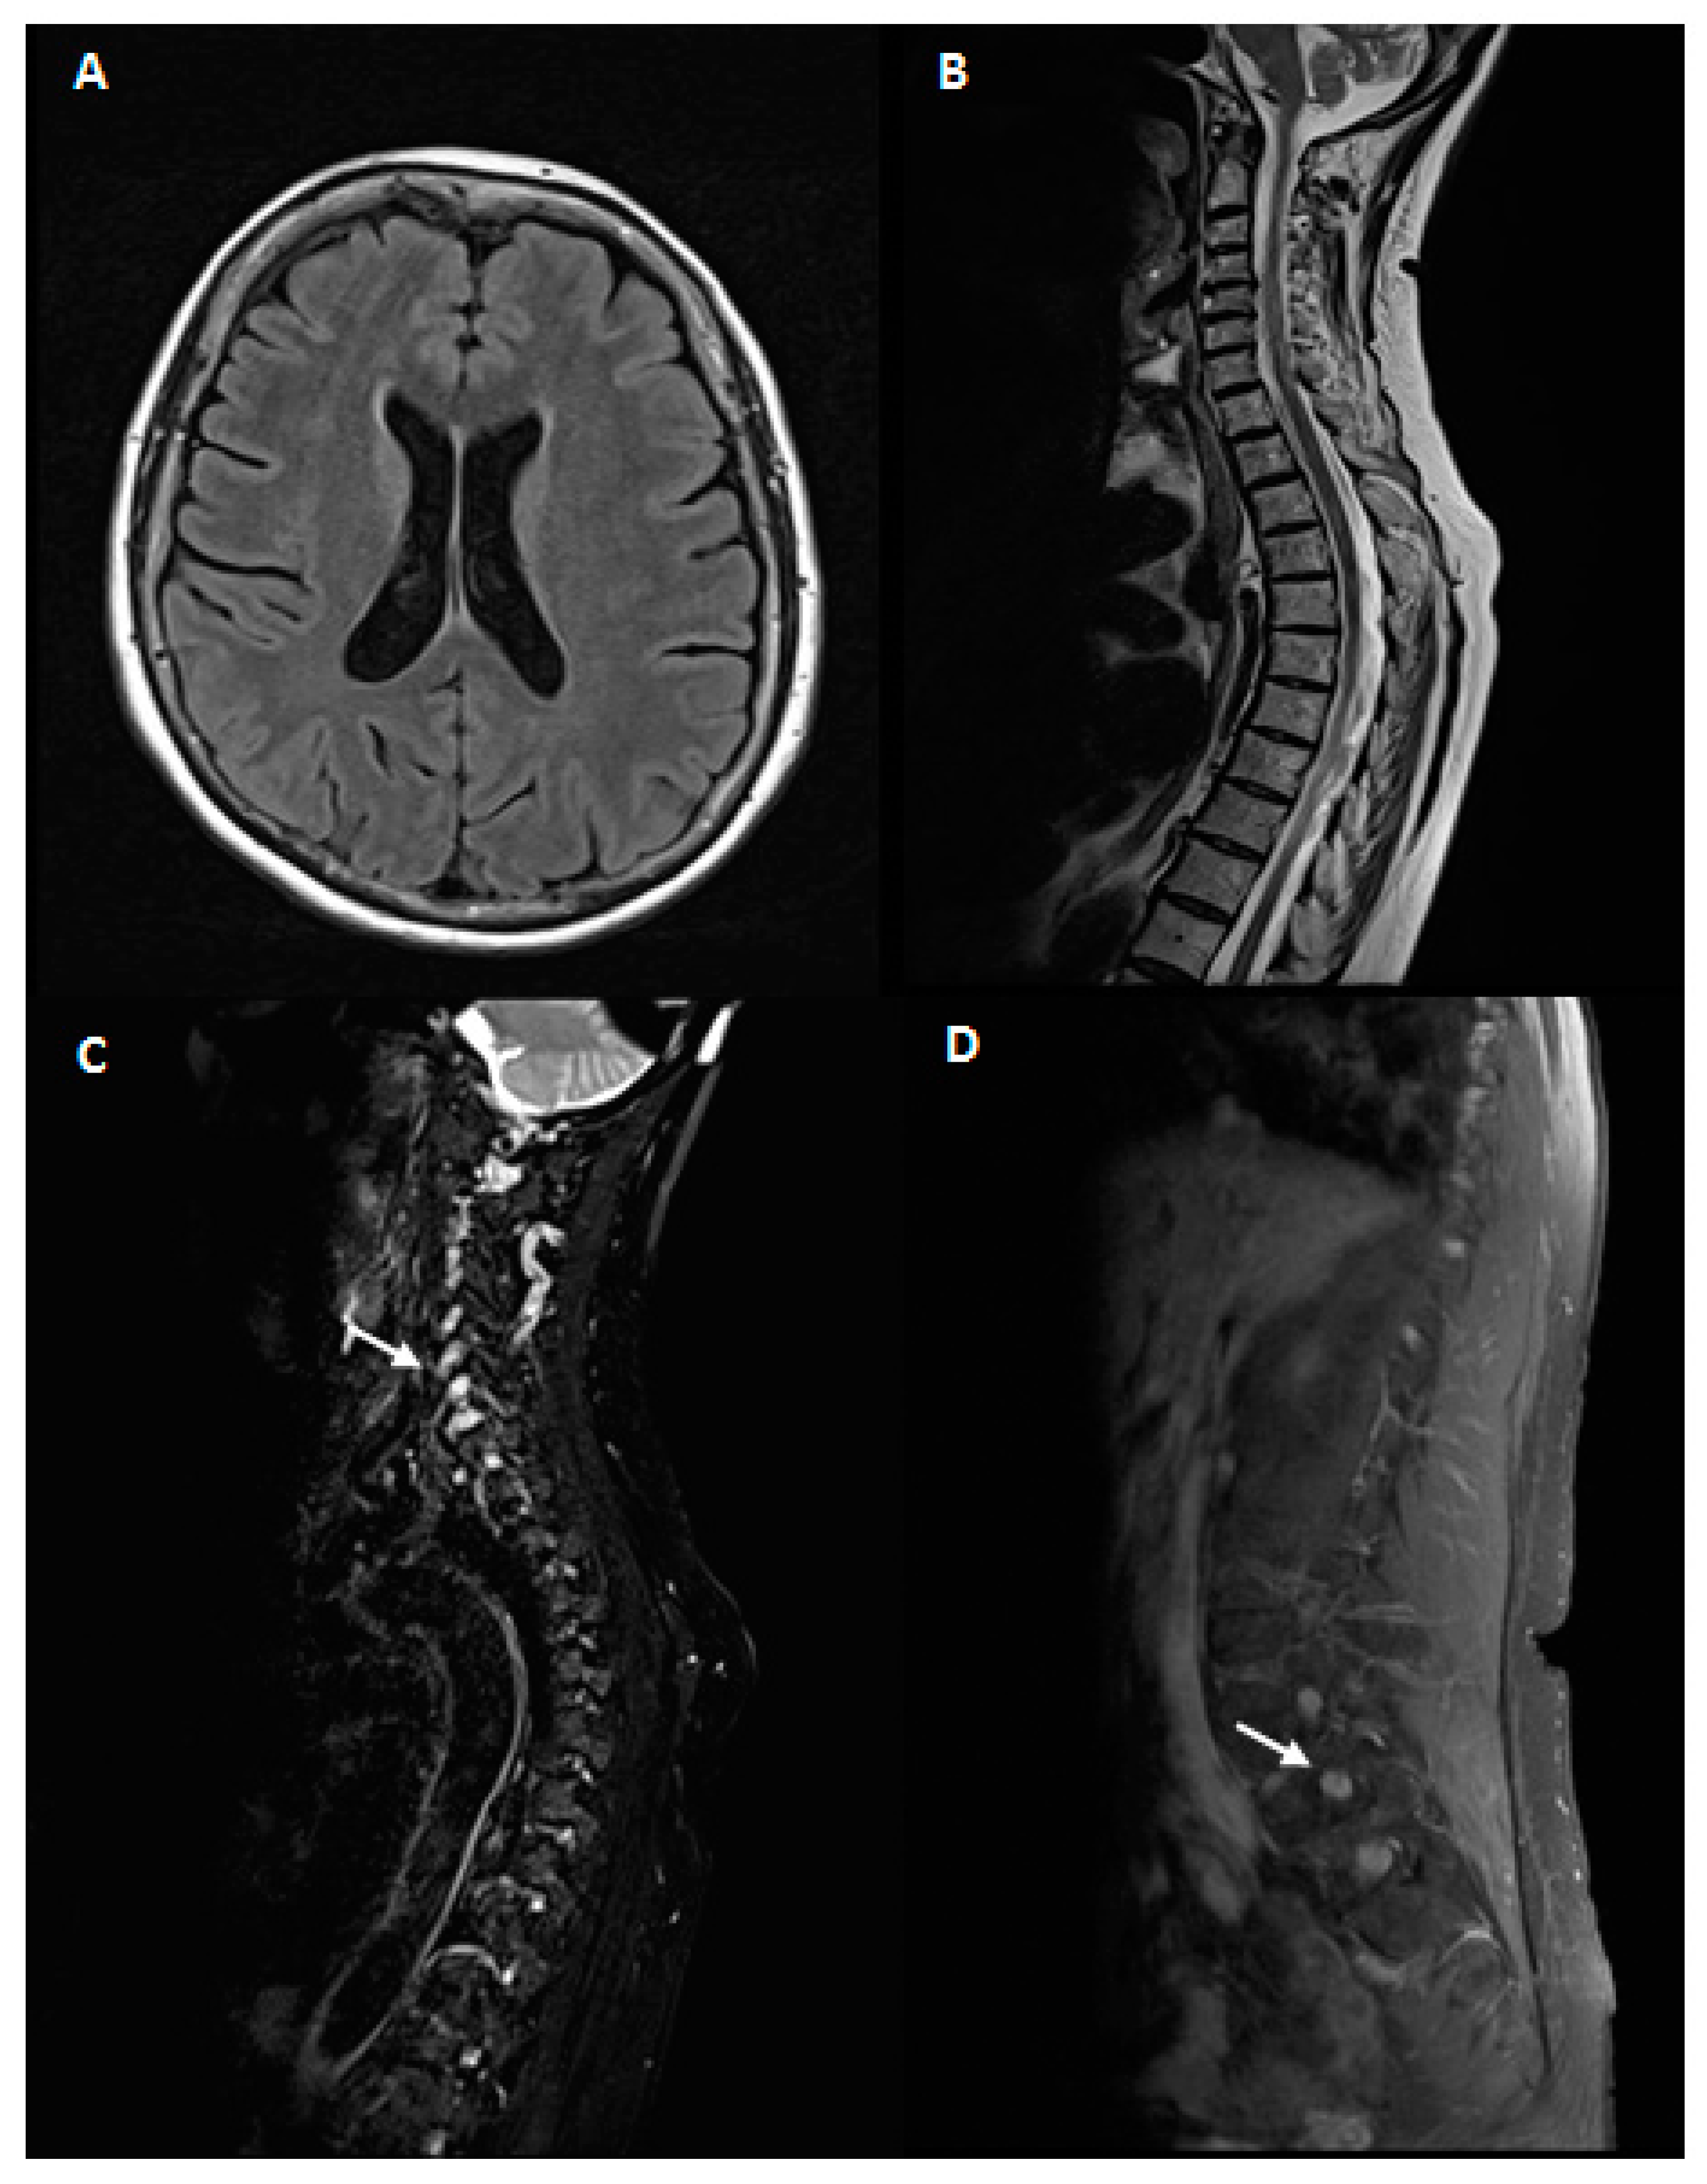

Brain and spinal cord MRI showed an enlargement of cervical and lumbar roots without gadolinium enhancement as for chronic roots inflammation, in absence of intramedullary lesions Figure 1.

Figure 1. Magnetic resonance imaging(MRI)study. 1.5 Tesla brain and spinal cord MRI. A, B: brain MRI axial T2 fluid-attenuated inversion recovery (FLAIR) (A) and spinal cord MRI sagittal T2 fast spin echo (FSE)(B) of our patient. No abnormalities were noticed. (C,D): Fat-suppressed T2 sequences of cervical (C) and lumbar (D) MRI scans showing hypertrophy of hyperintense nerve roots (white arrows).